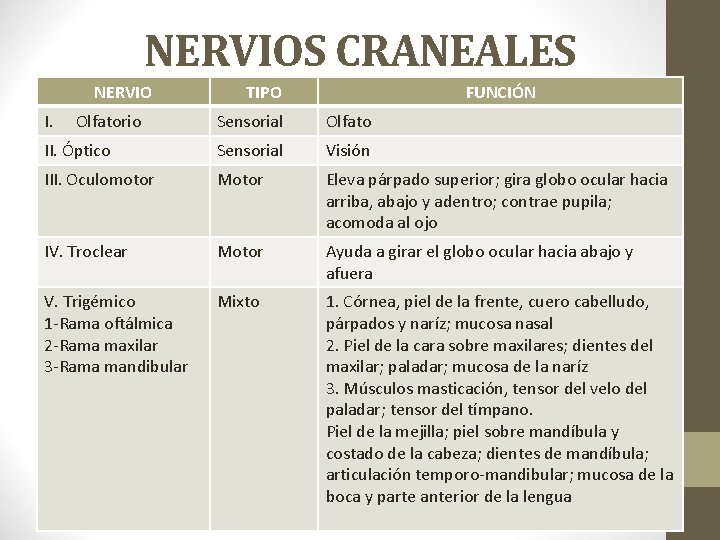

NERVIOS CRANEALES

NERVIOS CRANEALES NERVIO I. Olfatorio TIPO FUNCIÓN Sensorial Olfato II. Óptico Sensorial Visión III. Oculomotor Motor Eleva párpado superior; gira globo ocular hacia arriba, abajo y adentro; contrae pupila; acomoda al ojo IV. Troclear Motor Ayuda a girar el globo ocular hacia abajo y afuera V. Trigémico 1 -Rama oftálmica 2 -Rama maxilar 3 -Rama mandibular Mixto 1. Córnea, piel de la frente, cuero cabelludo, párpados y naríz; mucosa nasal 2. Piel de la cara sobre maxilares; dientes del maxilar; paladar; mucosa de la naríz 3. Músculos masticación, tensor del velo del paladar; tensor del tímpano. Piel de la mejilla; piel sobre mandíbula y costado de la cabeza; dientes de mandíbula; articulación temporo-mandibular; mucosa de la boca y parte anterior de la lengua